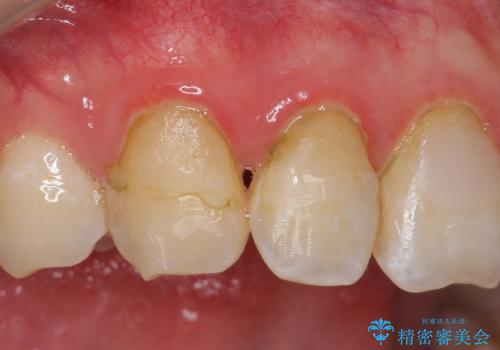

- 右上2、3番目の歯の色・形が気になるといらっしゃった方の症例です。

古い樹脂を除去後、オールセラミッククラウンによる補綴を行いました。